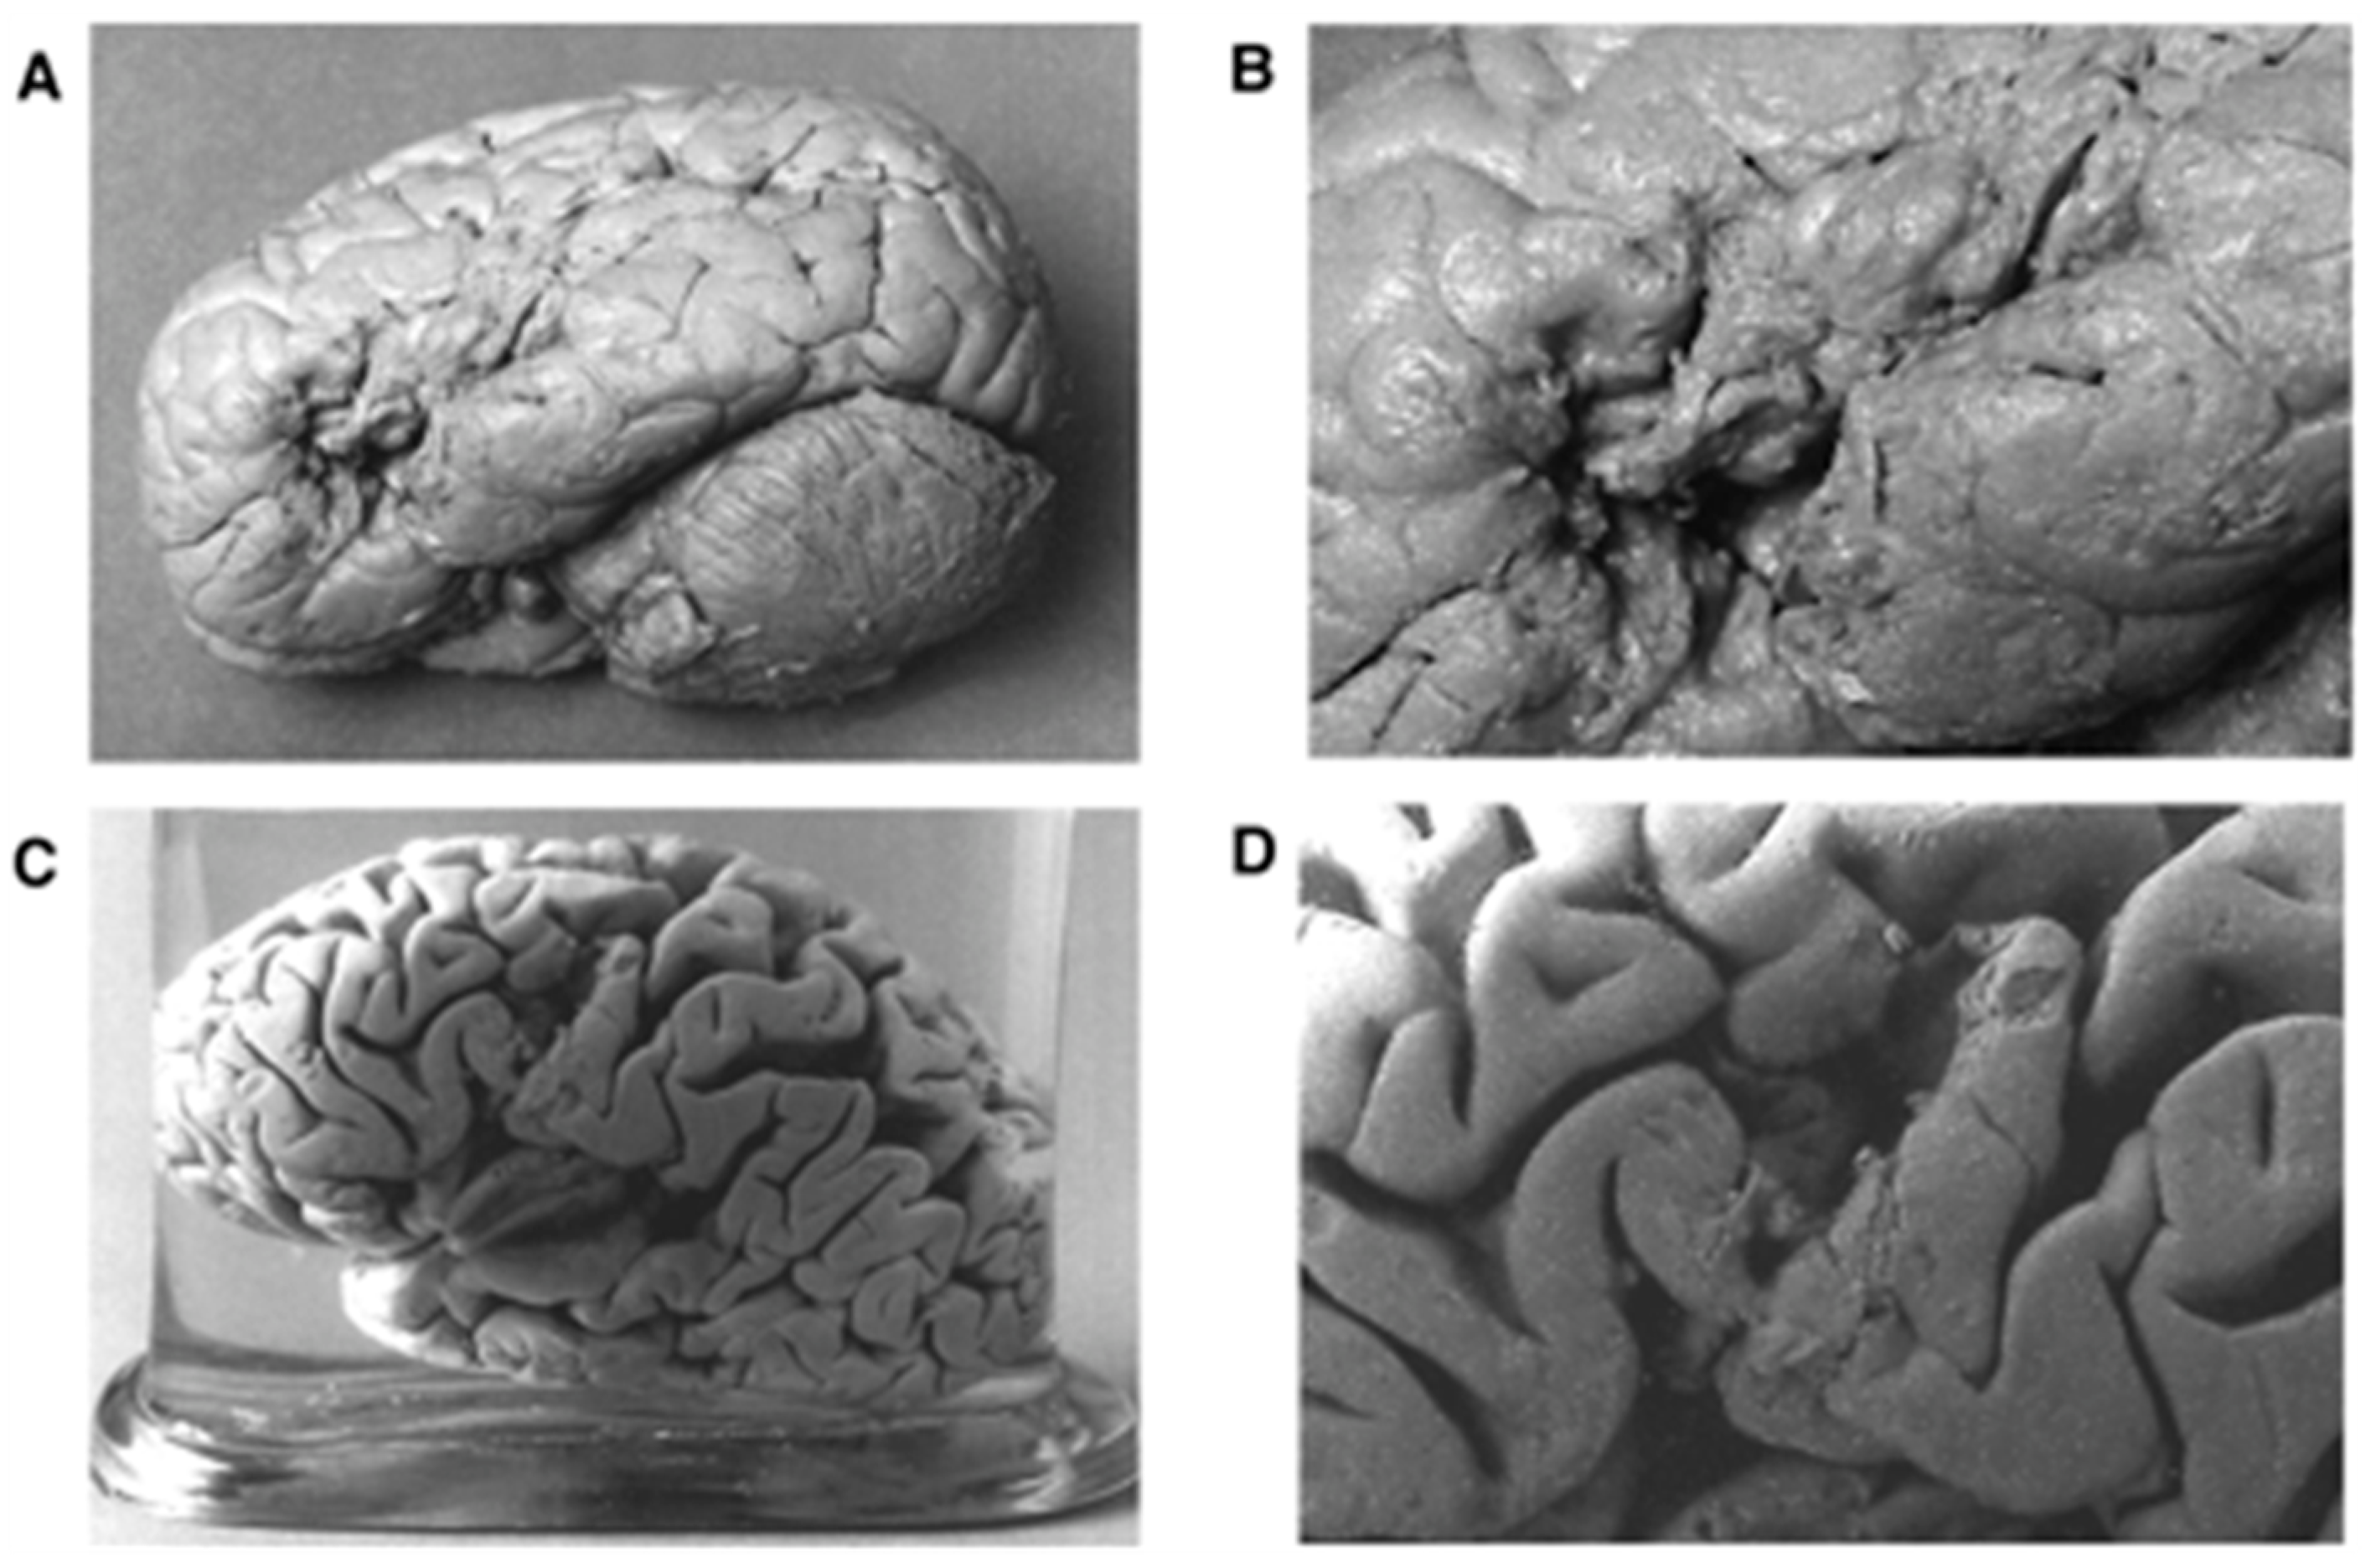

2. The Past